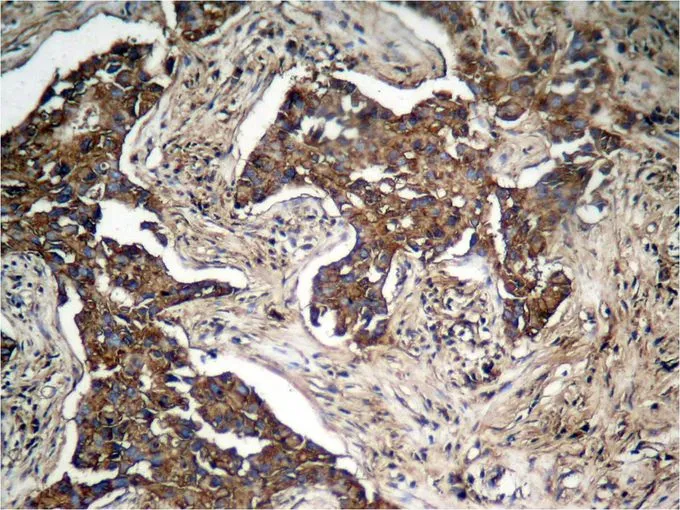

ApplicationsImmunoFluorescence, Western Blot, ImmunoCytoChemistry, ImmunoHistoChemistry, ImmunoHistoChemistry Paraffin

- ApplicationsImmunoFluorescence, Western Blot, ImmunoCytoChemistry, ImmunoHistoChemistry, ImmunoHistoChemistry Paraffin